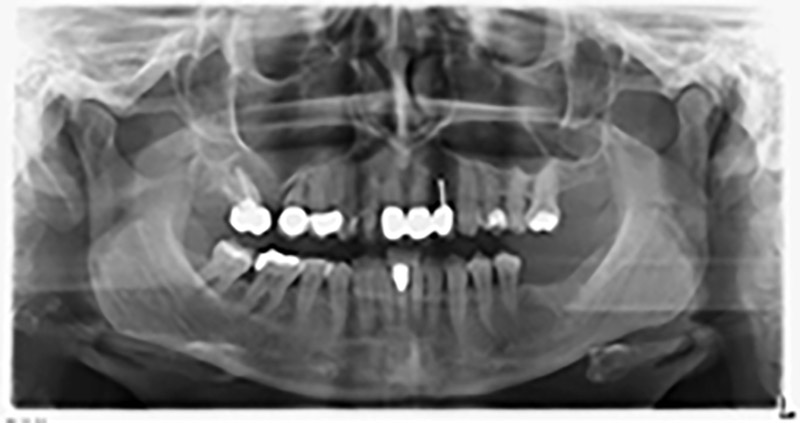

La paciente de 59 años presentaba una periodontitis avanzada, describía una desagradable sensación y un mal gusto proveniente del primer cuadrante. La evaluación clínica mostró en general marcadas profundidades de bolsa y una degeneración ósea muy avanzada en las regiones 16 y 14. El estudio radiológico corroboró estos resultados (figura 1). Las piezas dentales 16 y 14 no podían conservarse.

Imagen 1: Ortopantomografía con retirada ósea en las regiones 16 y 14*